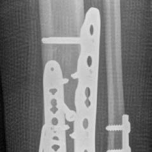

Removal of implants is not mandatory but recommended if implants are prominent under the subcutaneous envelope of the distal tibia. Implant removal should be undertaken only after healing is complete, ie, after 1 year at the earliest. This patient had achieved good radiographic and functional healing at the 1-year postoperative review (Fig 2.2-8 and Fig 2.2-9).

Fig 2.2-8a–b Postoperative x-rays at 1 year showing healed fractures, implants in situ, and limited tibiotalar arthrosis.

1. AP view.

2. Lateral view.